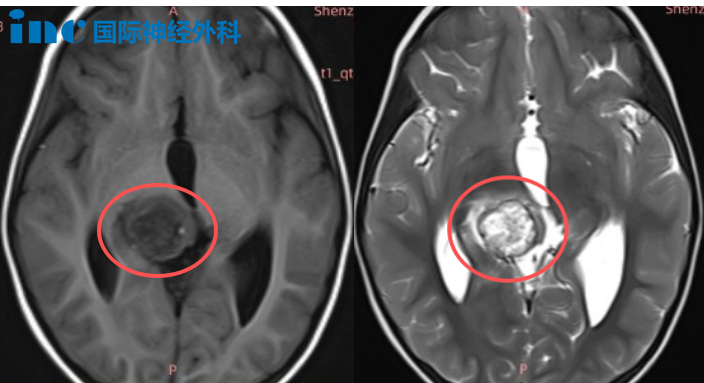

命运给26岁的菲力带来了严峻挑战:生长于丘脑的肿瘤,正侵蚀其...